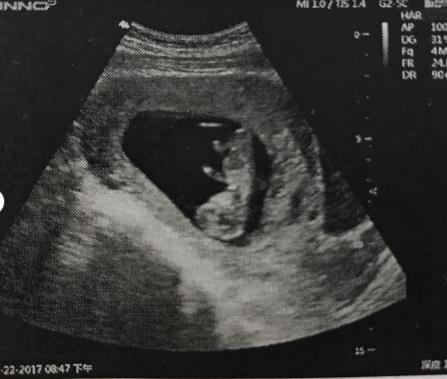

我是在公立医院生宝宝,每家医院会有不同,我的大致流程是1️⃣确定怀孕后在医院预约建档2️⃣在网上填写生育服务单经审核后打印3️⃣末次月经49天后去医院做B超,排除宫外孕,要可见胎心胎芽确保宝宝正常发育(❗️划重点:去早了可能B超无法监测到,去晚了可能影响建档和后续检查,一般是50天左右)4️⃣拿着B超单、生育服务单、夫妻各种证件(我是身份证、结婚证、户口本全揣着)去户口所在地的社区医院领北京市母子健康手册5️⃣拿着母子健康手册回医院,医生会开很多检查项目,需要空腹抽血和妇科检查,包括血尿常规、甲功、肝功、血型鉴定、病毒感染、心电图等等(和孕检一些项目重复,由于我时间间隔特别近所以直接省掉了一些)6⃣️这些检查结果没有问题的话会汇总在一起,给一个牛皮袋就算正式建档了,它会伴随整个产检、生产直到产后42天复查。

♀️侧脑室增宽:第一次排畸B超时提示宝宝双侧脑室增宽,左侧0.82cm、右侧0.76cm。在网上查资料后把我和家人担心坏了,正常情况超过0.5cm就会提示,医生只说脑脊液会慢慢吸收,不超过1cm就没事,等复查再看看。第二次排畸B超时左侧0.75cm,右侧0.53cm,我总算安心一点儿。可是30W的时候右侧没事左侧居然1.1cm,我都吓傻了,找了认识的医生,她让我放宽心再观察。所幸32W时左侧0.61cm、右侧0.7cm。

❗️划重点:通过查资料我了解到大脑的腔隙被称为脑室,侧脑室就是其中之一,里面有脑脊液,在这些脑室里流动形成循环。如果由于某种原因使脑脊液循环途径受阻,就会发生脑室扩张或脑积水。宝宝脑部发育高峰期是会出现暂时性增宽,后期会慢慢吸收,真正不可逆的情况可能是先天性遗传或者病变(如弓形虫感染),唐筛就是排除先天缺陷的手段,我唐筛结果正常。医生告诉我B超结果与设备、操作人员、造影角度有很大关系,所以是存在误差的,不能以某次检查结果定论。